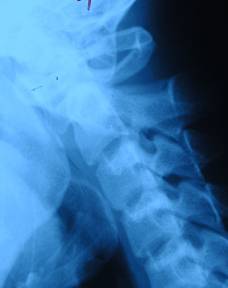

寰樞關節脫位除外上頸椎的其他部位損傷,必須藉助X線攝片X線張口位攝片,主要特徵表現是樞椎齒狀突與寰椎兩枚側塊間距不對稱。但張口拍片時合作不好可使投影位置偏斜,引起兩者間隙異常,或不能滿意顯示該區解剖結構。必要時多拍幾次片,排除因投影位置不當造成誤診,側位X線片能清醒顯示齒狀突和寰樞椎弓之間的距離變化。正常情況下在3mm以內,必要時CT掃描,與寰椎椎弓骨折及上頸椎畸形鑑別。應注意嚴重的陳舊性半脫位,表現為斜頸及運動受限,頸部活動時疼痛。可導致面部發育不對稱斜,頸的出現可引起對側胸鎖乳突肌痙攣。

1、X線檢查:

寰樞關節脫位2、CT檢查:

可與寰椎椎弓骨折及上頸椎畸形等疾病相鑑別,特別在頸部有創傷史,有頸部疼痛,僵硬或固定體位。而x線未發現異常時,CT檢查有助於防止漏診。